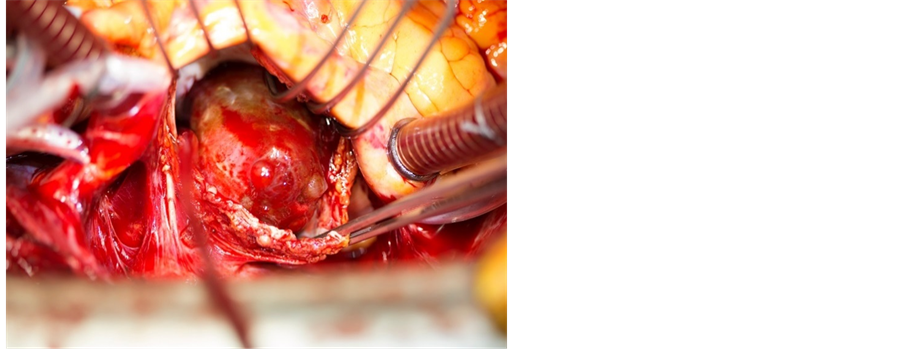

The patient underwent surgical treatment with a median sternotomy, and during surgery a tumour the size of a golf ball was removed (Figure 4). Histologically, it proved to be myxoma (Figure 5). The patient had an uneventful postoperative course and was discharged 5 days after the surgery in well-being. Echocardiography performed four months after the surgery showed no evidence of myxoma recurrence and the patient was asymptomatic, without adverse events.

Figure 4. Photograph showing the resected left atrial mass. The red line on the right picture shows the attachment of the myxoma.